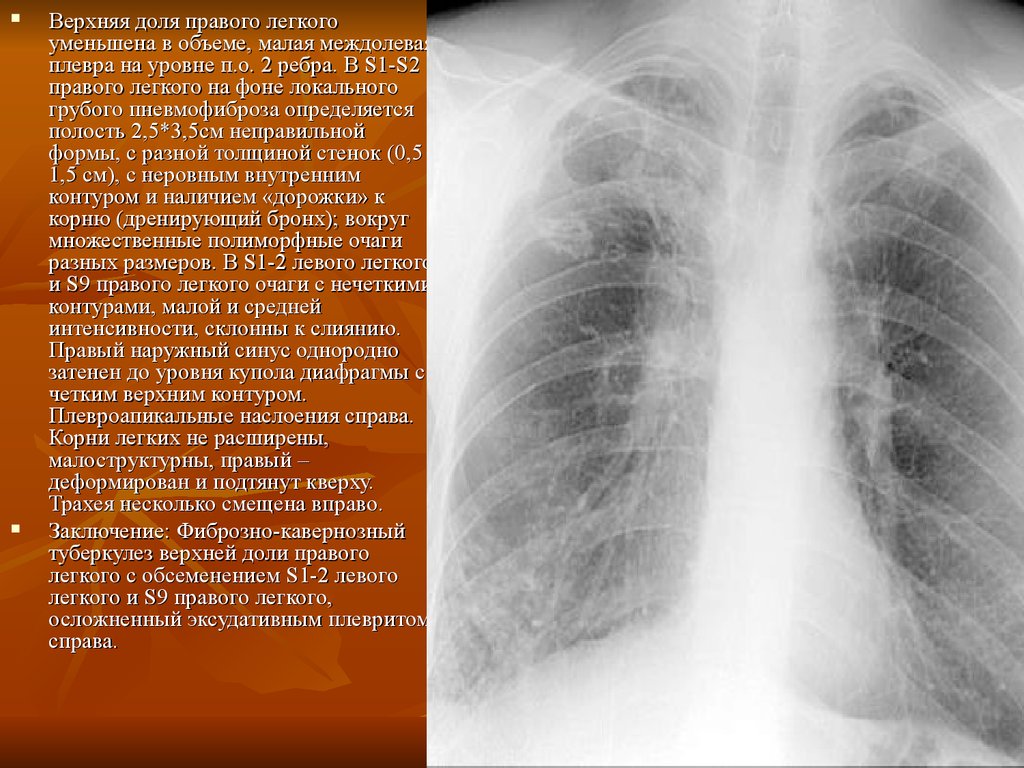

.jpg)